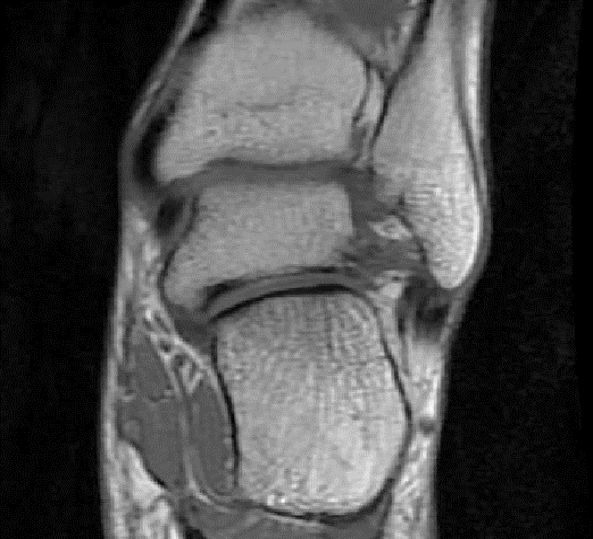

从这张片子我们可以看到正常的韧带结构,包括距腓前韧带,跟绯韧带,它是质地比较均一,T2相高信号,连续性良好,并且有良好的张力,从冠状位也可以看到跟绯韧带,在腓骨肌腱的深方,也是T2相跟T1相的低信号,有良好的连续性,张力也不错。